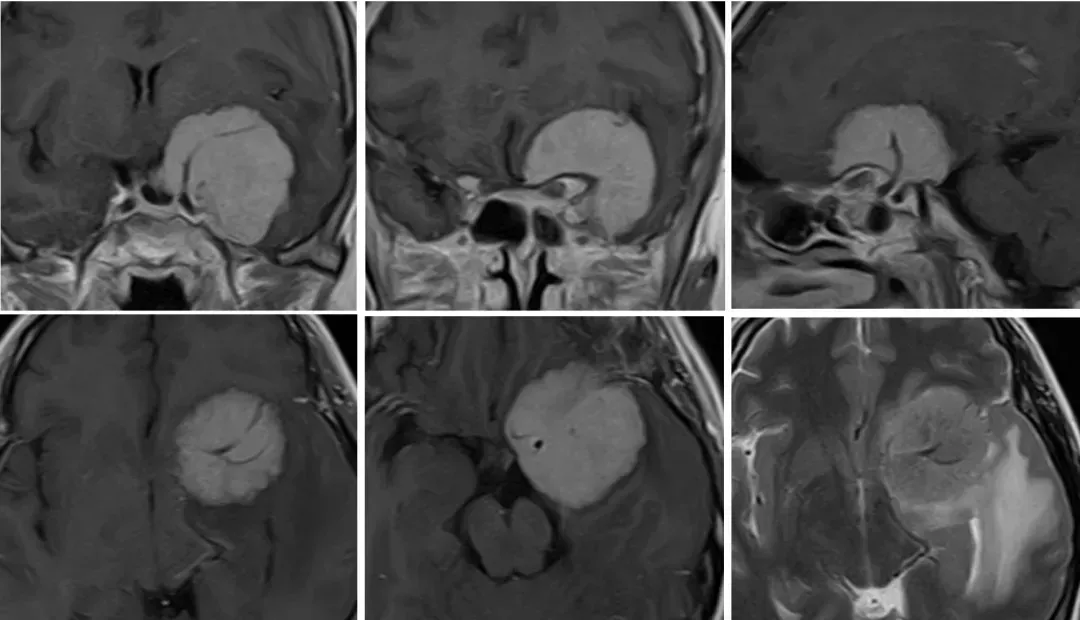

视力不断下降,以至于右眼失明,仅残存微弱的光感。经医生检查发现,陈女士“视力下降、视力减退明显伴视野缺损”,被确诊为前床突脑膜瘤,且肿瘤比较大。

前床突脑膜瘤(anterior clinoidal meningioma,ACM),即蝶骨嵴内侧型(床突型)脑膜瘤,通常归类于鞍旁脑膜瘤或蝶骨嵴脑膜瘤,起源部位很难确定,有时会与起源于鞍结节、鞍膈、视神经管的脑膜瘤相混淆。ACM通常位于前床突及蝶骨嵴内侧1/3,由于肿瘤倾向于向前床突及蝶骨嵴外侧延伸,巨大ACM会侵犯颈内动脉及其分支、海绵窦等重要血管结构,同时肿瘤与视神经、动眼神经的紧密关系更增加了手术难度。尽管颅底显微外科技术进展迅速,但如何完整、安全地切除ACM对于神经外科仍然是一个巨大的挑战。

前床突脑膜瘤诊断

术前CT可以检测肿瘤内钙化的存在,预测手术时是否会出现更坚固和纤维状的肿瘤。骨CT还可以添加关于肿瘤起源部位骨质增生的有用信息,该部位的骨质增生程度从轻微到严重不等。此外,它还提供了关于前床突解剖、其气化、颈动脉床突孔的存在和周围骨结构的重要信息。现在常规进行对比增强MRI,以研究肿瘤与周围解剖结构、视管和眶上裂侵犯、血管包裹和海绵窦侵犯的关系。肿瘤体积测量通常有助于顺序评估非常小的肿瘤的手术适应症,也有助于评估手术和/或放射治疗的疗效。

文献支持使用完整的术前神经放射学检查,包括MRI、CT扫描、CTA和/或MRA。高质量的T2和T1成像技术(CISS和VIBE)可用于增加视神经管和海绵窦内肿瘤扩展的可视化。在目前的实践中,可以在选定的情况下考虑DSA。(C级)

大型前床突脑膜瘤是从前床突起源的,通常压迫并包裹附近的神经血管结构,如颈动脉和视神经。部分可能会长到蝶骨嵴内侧区域并与蝶骨嵴内侧脑膜瘤相混淆;当床突脑膜瘤生长到非常大时,它们可能波及到鞍旁区域,在其前后和中外侧延伸,在这种情况下,肿瘤可以横向延伸到海绵窦或向后延伸到后床突和岩斜区。

大多数经验丰富的外科医生都认为它是具挑战性的脑膜瘤之一,因为它们多包绕颈内动脉(ICA)及其分支大脑中动脉(MCA),并侵入海绵窦和视神经管。在很多情况下,肿瘤与颈动脉紧密黏附,因此即使在经验丰富的手中也很难完全切除肿瘤。